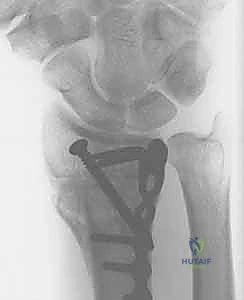

5. التثبيت بصفائح التيتانيوم (Internal Fixation)

للحفاظ على الوضع الجديد والمثالي للعظم، يتم استخدام صفائح تيتانيوم متقدمة ذاتية الغلق (Volar Locking Plates). هذه الصفائح مصممة تشريحياً لتلائم شكل الكعبرة، وتوفر تثبيتاً قوياً جداً يسمح للمريض ببدء تحريك أصابعه في اليوم التالي للعملية.

عملية تصحيح تشوه الكعبرة البعيدة (Corrective Osteotomy): خطوة بخطوة

تُعد هذه الجراحة من روائع جراحة العظام الحديثة. الهدف ليس فقط "كسر العظم وإعادة تجبيره"، بل هو إعادة بناء هندسي دقيق لمفصل الرسغ. إليكم كيف يجري الأستاذ الدكتور محمد هطيف هذه الجراحة المعقدة: